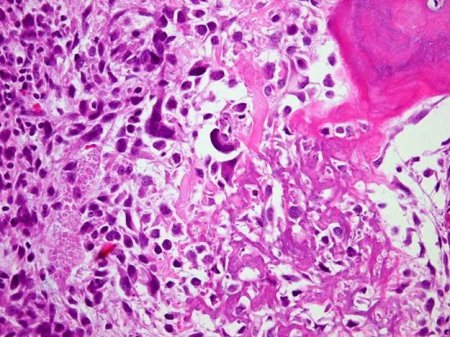

Osteoblastic osteosarcoma; lace-like osteoid in a highly pleomorphic sarcomatous stroma

Personal collections of Dr Michael J. Klein and Dr Luminita Rezeanu